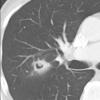

Halo sign

Date: 04/28/2014

Views: 3682